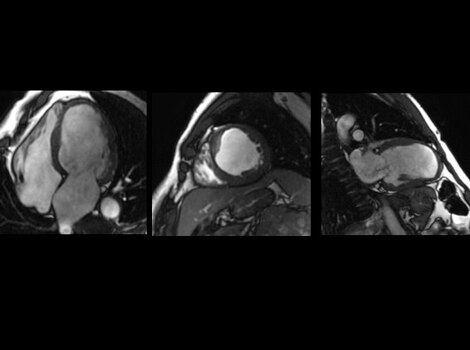

SIGNA Works CV Imaging & Analysis Tools

One non-invasive CMR exam to assess cardiac morphology, function, flow, tissue viability and coronary anatomy without ionizing radiation. Read More

SIGNA™ Works CV Imaging & Analysis Tools